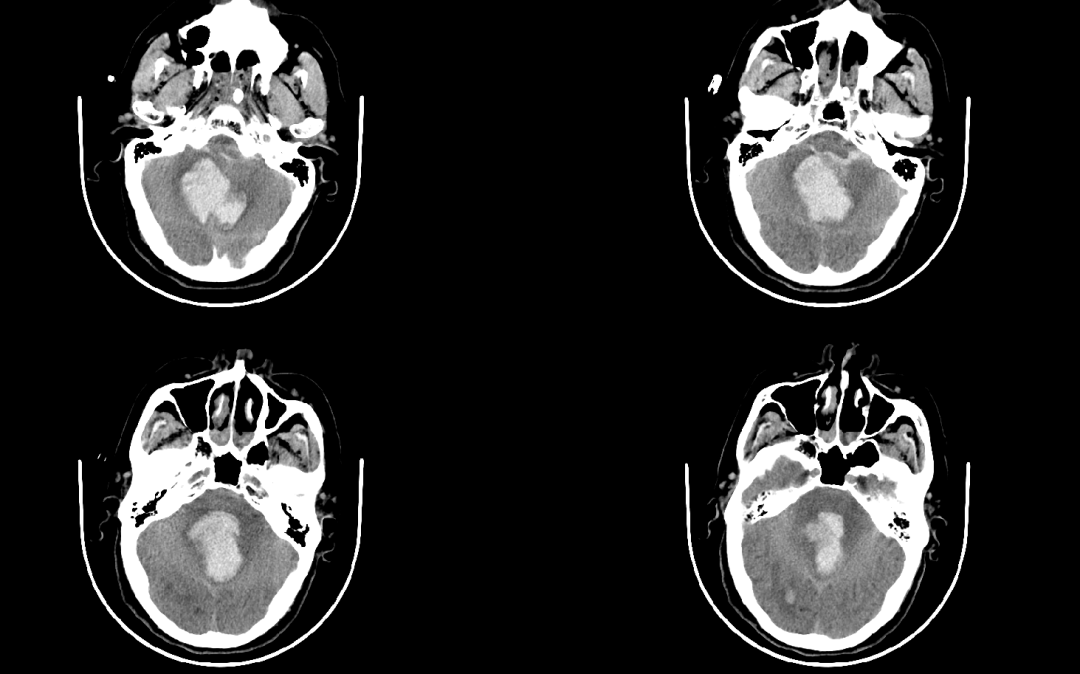

病例1

患者因“突發(fā)意識不清2小時”入院。行急診CT檢查提示:“小腦出血并破入腦室”,出血量達45毫升,病情嚴重,神經(jīng)外科團隊馬上制定手術方案,行急診顯微鏡下小腦血腫清除術,手術過程順利,術后復查血腫完全清除,經(jīng)過康復和護理,患者神志漸清,目前已順利出院。